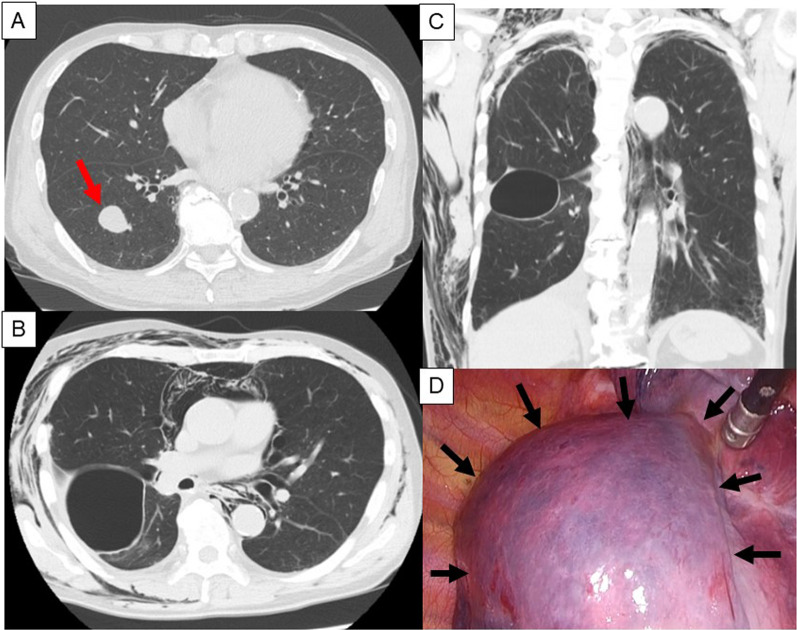

Fig. 1.

Preoperative CT and newly formed pulmonary cyst in Case 1. Preoperative CT showing a nodule of 23 mm in the middle of the right lower lobe (arrow). CT reveals few fibrotic changes; however, the patient was diagnosed with interstitial pneumonia by histopathology of the resected lung (A). Postoperative CT performed on POD 17 shows a newly developed pulmonary cyst at the upper interlobular surface of the middle lobe with subcutaneous emphysema and pneumomediastinum (axial section: B, coronal section: C). A broad-based pulmonary cyst is observed during reoperation (arrows) (D)

A man in his 70 s underwent right lower lobectomy using uniportal video-assisted thoracoscopic surgery (VATS) for a solitary metastatic lung tumor from undifferentiated pleomorphic sarcoma of the lower extremity (Fig. 1A). Smoking history was 43 pack-years. The preoperative pulmonary function test (PFT) demonstrated forced vital capacity (FVC) was 4050 mL (%FVC 113.1%), and the ratio of forced expiratory volume in 1 s to FVC (FEV1.0%) was 77.5%. The lung was completely lobulated, and we did not need to use staplers to divide the fissure. The intraoperative sealing test revealed no air leakage. The pathological diagnosis was metastasis of undifferentiated pleomorphic sarcoma with interstitial pneumonia that was preoperatively undiagnosed using computed tomography (CT). The patient was discharged on postoperative day (POD) 6. The patient was re-admitted with subcutaneous emphysema and pneumomediastinum on POD 19. Computed tomography (CT) revealed a newly developed large pulmonary cyst in the middle lobe at the interlobar plane between the middle and upper lobes (Fig. 1B, C). No pneumothorax was observed. VATS was performed on POD 20. A pulmonary cyst was noted at the interlobar surface of the middle lobe, between the middle and upper lobes. (Fig. 1D). Blood clots and multiple air leakages were detected inside the cysts (Fig. 2A). After incision of the cyst wall, a polyglycolic acid (PGA) sheet and fibrin glue were applied inside the cyst (Fig. 2B). The cyst wall was sutured using a 4-0 absorbable monofilament suture (Fig. 2C) and covered again with PGA sheet and fibrin glue (Fig. 2D). Postoperative course was uneventful. CT 1 year after surgery showed no development of a pulmonary cyst or air space.